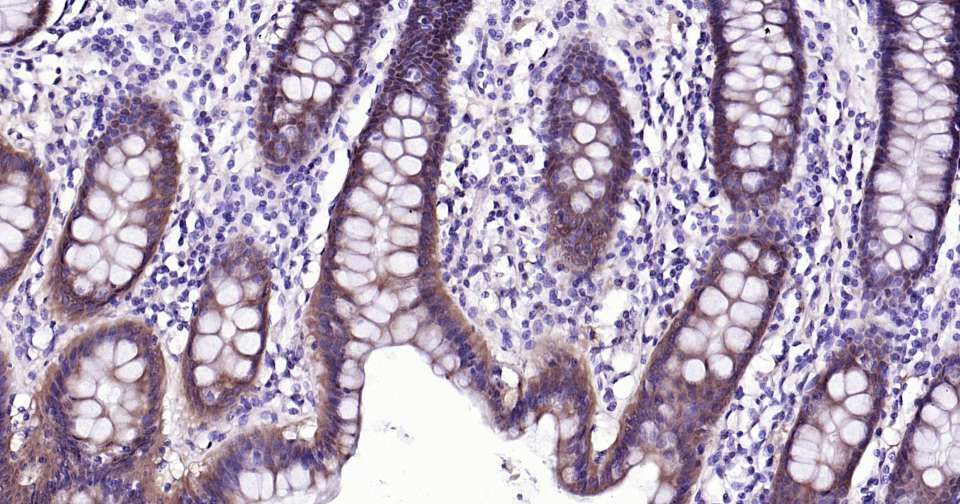

Immunohistochemical analysis of paraffin embedded human colon tissue slide using IHC0321 (Caspase-6 Kit).

Immunohistochemical analysis of paraffin embedded rat colon tissue slide using IHC0321 (Caspase-6 Kit).